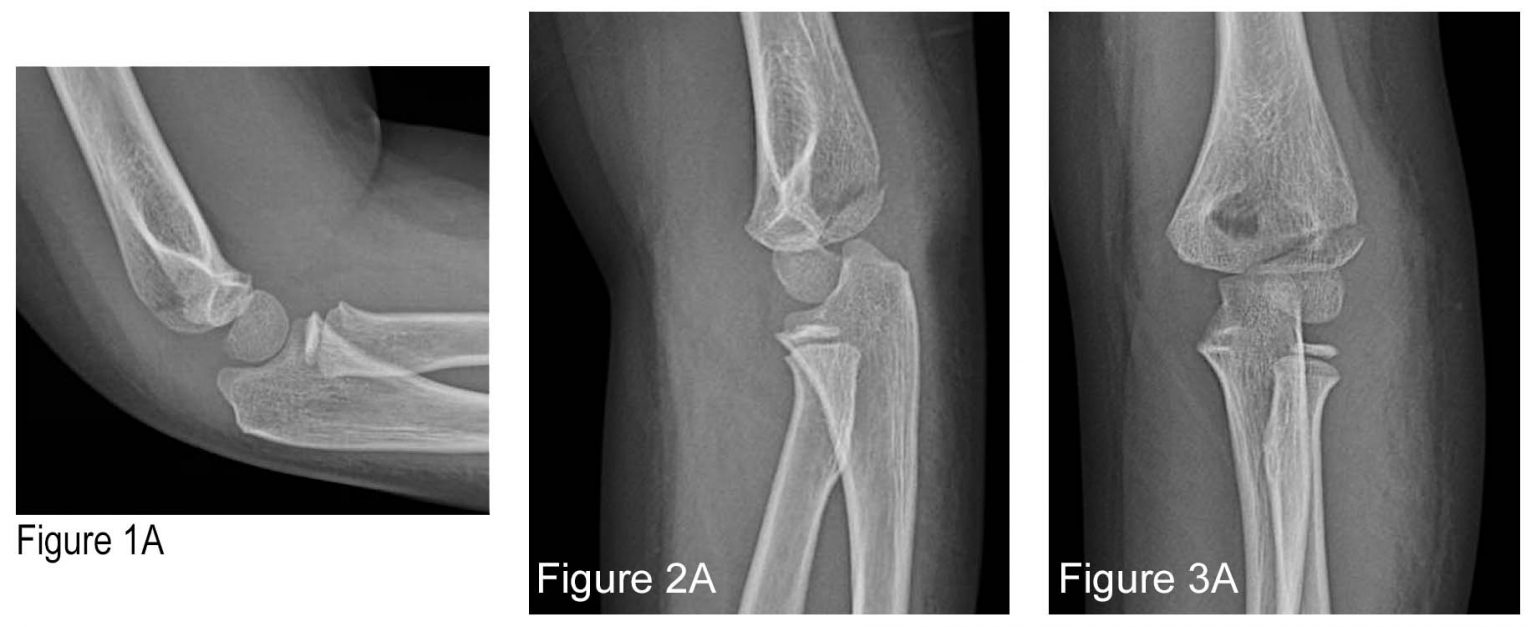

From www.acepnow.com

How to Avoid Missing a Pediatric Elbow Fracture ACEP Now Can You Bend Fractured Elbow You may hear or feel a pop or crack in. one of the main goals of physical therapy after an elbow fracture is to restore the normal range of motion (rom). Other signs and symptoms of a fracture. pain, bruising, and swelling around an elbow that’s hard to bend or twist can be signs of a broken elbow.. Can You Bend Fractured Elbow.

From openpress.usask.ca

Elbow Fractures Undergraduate Diagnostic Imaging Fundamentals Can You Bend Fractured Elbow Here are 6 signs that you may. an olecranon fracture is a break in the “pointy bone” of your elbow that sticks out when you bend your arm, which is actually the end of the ulna. an olecranon fracture usually causes sudden, intense pain and can prevent you from moving your elbow. one of the main goals. Can You Bend Fractured Elbow.